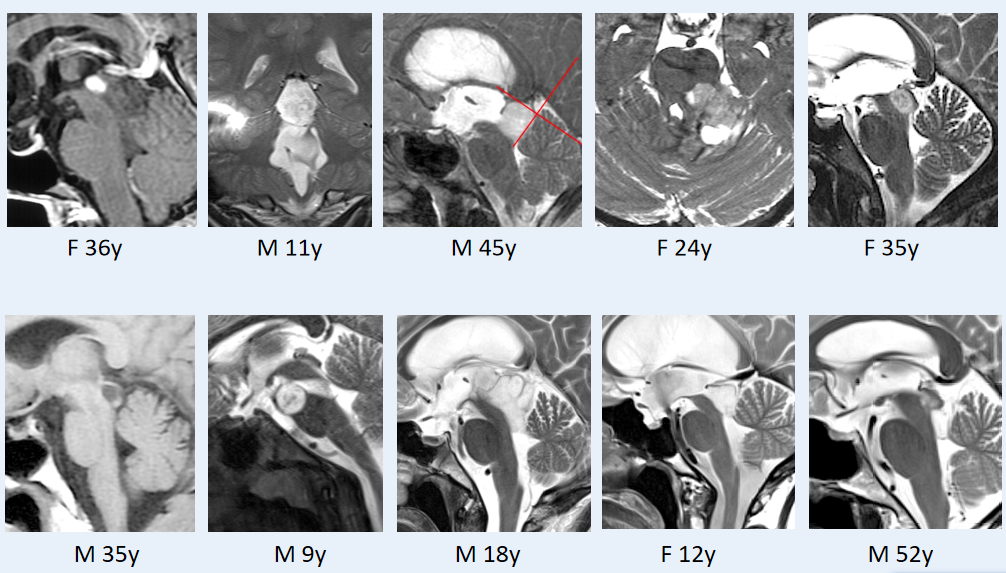

这些影像,你是否觉得熟悉?

对于脑干胶质瘤患者而言,这些影像再眼熟不过——病情的宣告,往往始于这一张张片子。

当被告知“无法手术”,当生存的希望一点点流逝,迷茫、绝望、勇气与坚韧在他们心中交织。一张张影像背后,是一个个鲜活的生命:9岁的孩童到52岁的成人,不同年龄、不同性别,却同样被脑干胶质瘤裹挟。

35岁的Emma,中脑顶盖肿瘤,内生性生长,仿佛被脑组织严密包裹,所幸尚未突破脑干表面。

术前MRI

巴教授选择了幕下小脑上旁中央入路,面对这个“很有弹性,容易‘溜走’”的肿瘤,巴教授手持CUSA刀(超声吸引器),击碎肿瘤然后再吸走。正常脑组织完好无损,而肿瘤被成功切除。

术后,患者短暂出现了帕里诺综合征,术后8周自行缓解。最终,病理报告显示:形成菊形团的胶质神经元肿瘤(RGNT)。术后5年随访时,MRI显示肿瘤无复发。术后12年的长期随访显示,她依然状态良好!